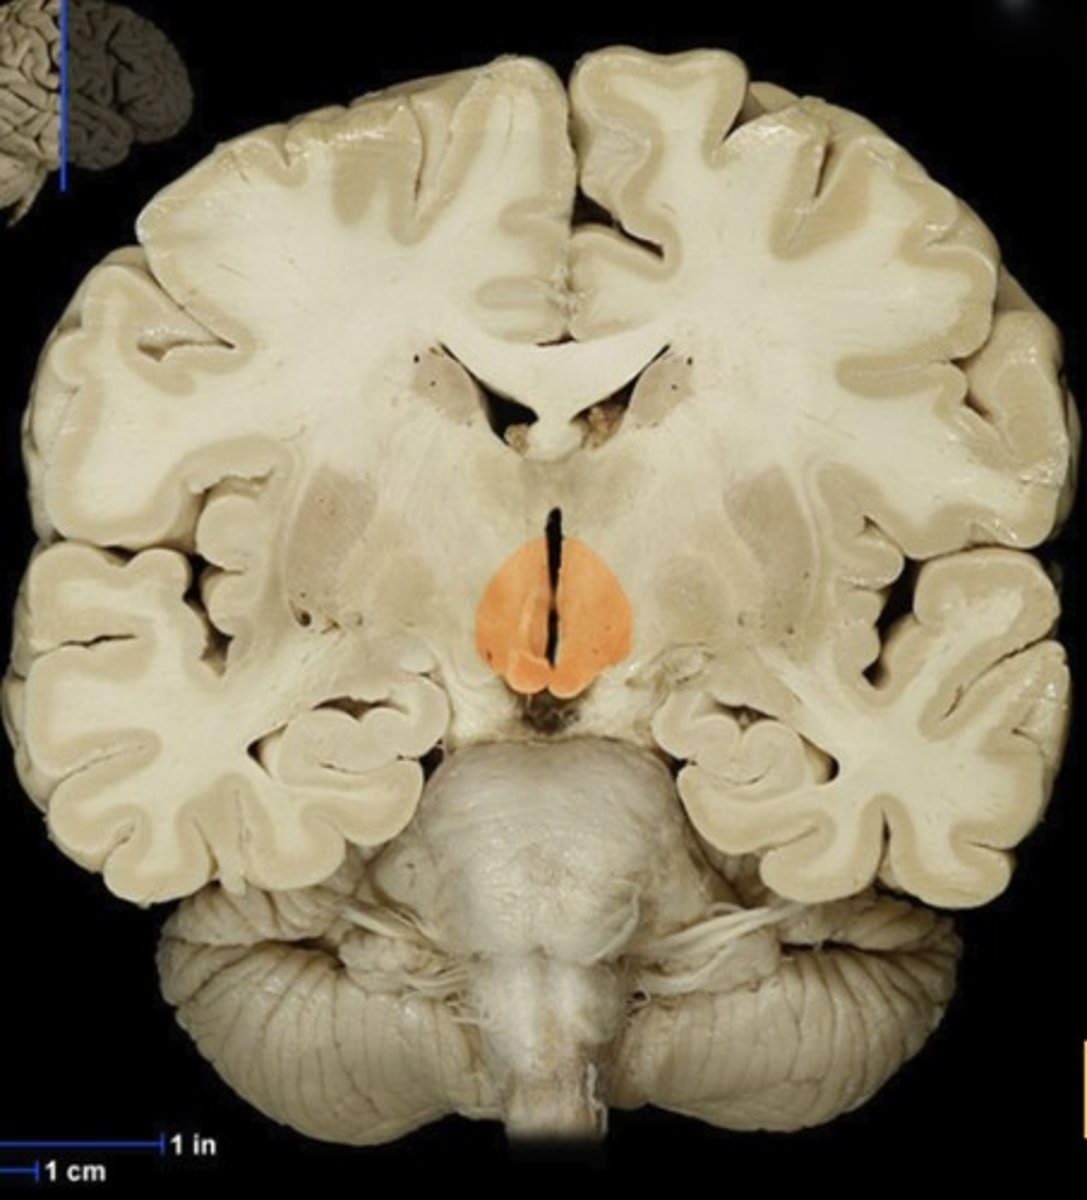

Caudate Nucleus

Name this structure

Gray matter (anterior view of coronal section)

Name this structure

White matter (anterior view of coronal section)

Name this structure

Corpus callosum

Name this structure

Fornix

Name this structure

Globus Pallidus

Name this structure

Hippocampus

Name this structure

Hypothalamus (anterior view of coronal section)

Name this structure

Lateral Ventricles

Name this structure

Mamillary body

Name this structure

Putamen

Name this structure

Thalamus (anterior view of coronal section)

Name this structure

Third Ventricle (anterior view of coronal section)

Name this structure